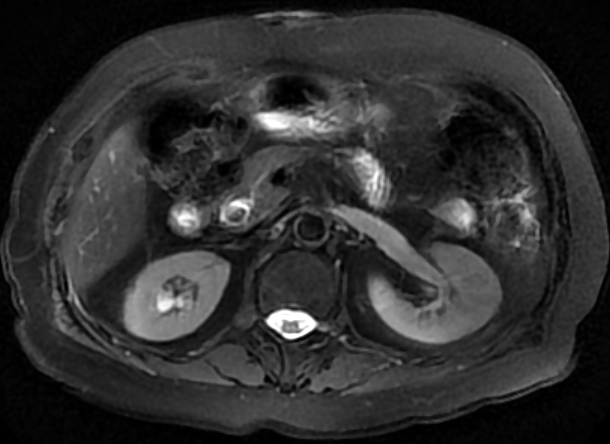

胆管结石患者核磁检查提示胆管末端存在结石

图片尺寸610x444